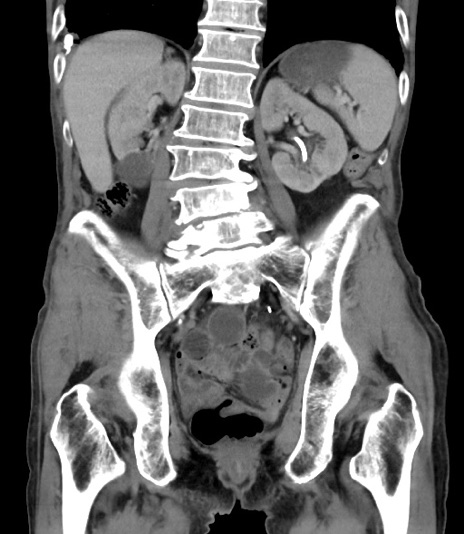

症例3(冠状断像)

【既往歴】膀胱癌にて膀胱全摘、両側尿管皮膚瘻